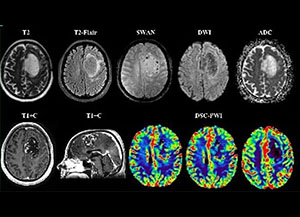

МРТ головного мозга и DSC-перфузия. Крупное интрааксиальное образование локализованное  в верхней лобной извилине левого полушария, окруженное перифокальным отеком ( с наличием феномена несоответствия Т2-Т2flair (mismatch sign)), с частичным вовлечением тела мозолистого тела. Видимого ограничения диффузии не отмечается, однако есть некая неоднородность в структуре опухоли, отчетливо визуализируется сеть патологически расширенных сосудов на ИП SWAN, а так же узловое накопление парамагнетика образованием на постконтрастных Т1-ВИ с отчетливо повышенными значениями rCBV в 5-7 раз по периферии.